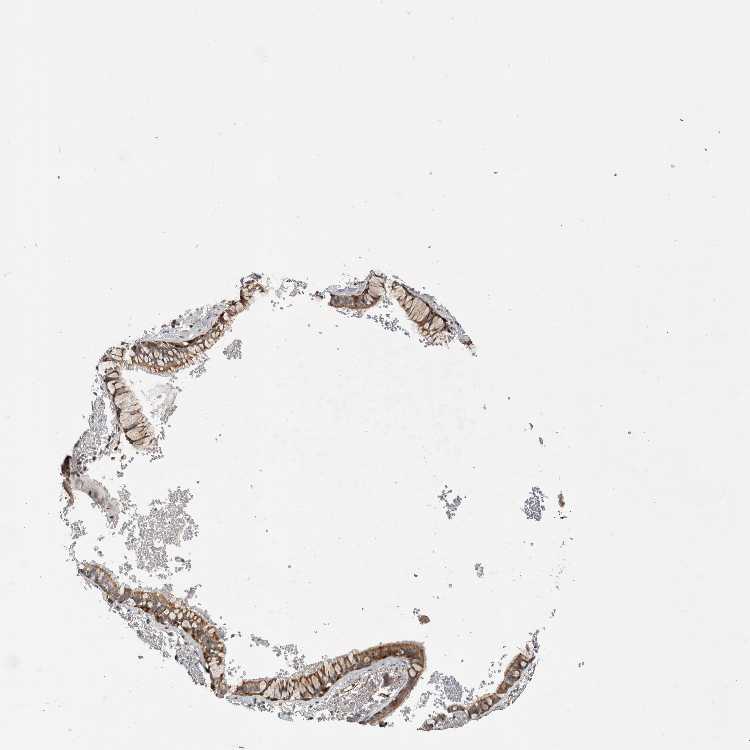

SOFT TISSUE 1 - Antibody stainingi

Antibody staining in the annotated cell types in the current human tissue is reported as not detected, low, medium, or high, based on conventional immunohistochemistry profiling in selected tissues. This score is based on the combination of the staining intensity and fraction of stained cells.

Each image is clickable and will lead to virtual microscopy that enables deeper exploration of all samples and also displays staining intensity scores, fraction scores and subcellular localization as well as patient and tissue information for each sample.

Antibody HPA018150Antibody HPA026834

Fibroblasts Not detectedNot detected

Peripheral nerve Not detected-

SOFT TISSUE 2 - Antibody stainingi

Chondrocytes -Not detected

Peripheral nerve Not detectedNot detected